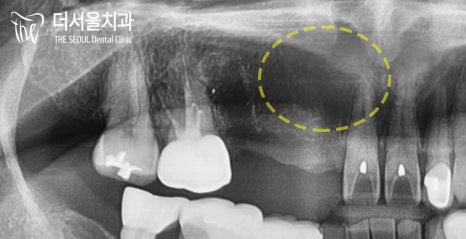

원래 있어야 될 위치에 있지 않고

잇몸 속, 입 천장에 묻혀 있는

말썽꾸러기 같은 곳이 있습니다.

바로 ‘ 매복치아 ‘ 죠.

인접치 뿌리에 가까이 있기 때문에

자칫 잘못하면 신경을 건드릴 수도 있죠.